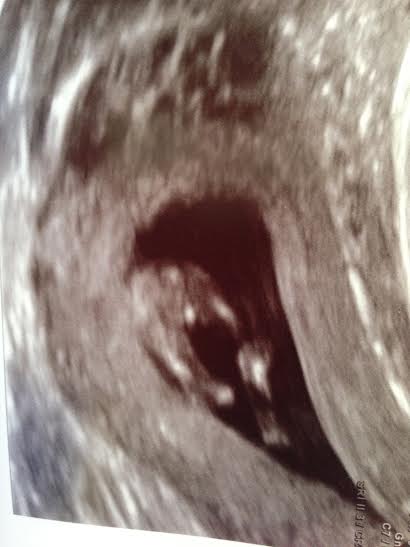

From my NT Scan this morning. 11weeks5daysAttachment 17876Attachment 17875Attachment 17874

If that is the nub I see it looks very girly!

The nub looks very girly- it is before 12 wks though so a cautious girl lean- but it is nice and long and angled down

I agree! Looks very girly..but it is still early. Lots of hope for sure!!

Oo my goodness I hope you wonderful ladies are right! The baby's skull is looking boyish to me but I think the nub is giving me hope!!